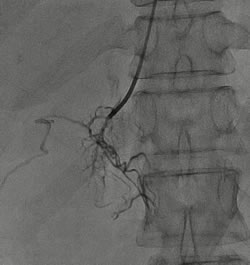

左侧肾上腺静脉插管采血 右侧肾上腺静脉插管采血

张女士是一名55岁的高血压患者,血压最高时可达180-190/100-110mmHg,使用3-4种降压药血压勉强控制到140/90mmHg以下。我院心血管专家团队为其进行了醛固酮立卧位试验,提示卧位ARR(血浆醛固酮/血浆肾素)53.1,立位ARR58.20,肾上腺CT增强发现其左侧肾上腺长有腺瘤。在中国高血压联盟副主席、我院心血管内科主任林金秀教授的指导下,彭峰博士和蔡瀚医师借鉴北京阜外医院与上海瑞金医院的先进经验,通过“双侧肾上腺静脉采血”为张女士进行肾上腺腺瘤功能评估。3天后,血液检查结果提示,其左侧选择性指数2.45,证明采血成功(选择性指数>2),左侧肾上腺静脉血醛固酮与外周静脉血醛固酮的比值,较左侧肾上腺静脉血皮质醇与外周静脉血皮质醇的比值未见明显升高,说明张女士左侧肾上腺腺瘤为无功能腺瘤,无需手术治疗,药物控制血压即可。最后,专家团队悉心为张女士的用药进行了调整,在血压的到良好控制后,张女士顺利出院。